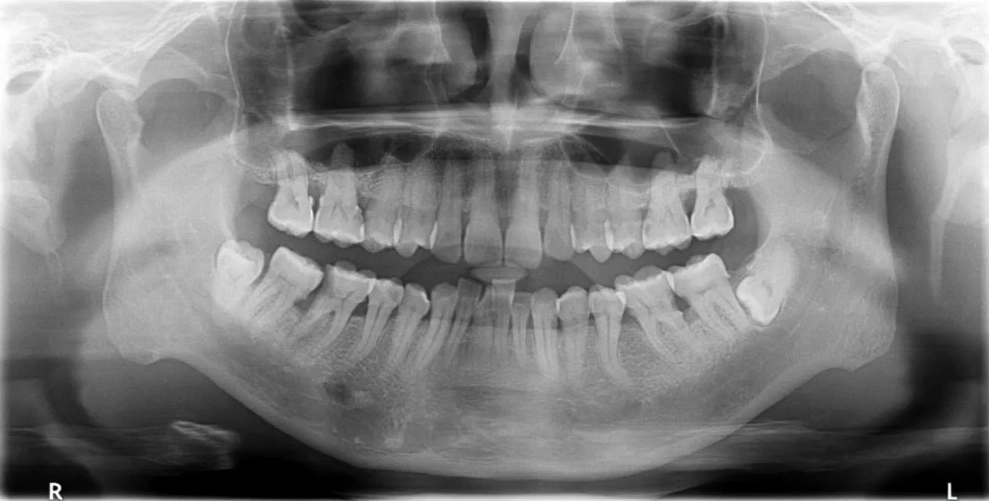

张XX,女,34岁

曲面断层片怎么看口腔精读 | 一次性教你看懂曲面断层片!_https://www.jmylbn.com_新闻资讯_第29张

1、牙槽骨水平性吸收,个别有垂直性吸收

2、全口结石影

治疗:洁刮治

检查:牙周探诊、咬合检查

正畸治疗考虑及设计

曲面断层片怎么看口腔精读 | 一次性教你看懂曲面断层片!_https://www.jmylbn.com_新闻资讯_第30张

3、牙缺失

治疗:种植治疗

检查:CBCT,对合牙

牙周治疗及维护

曲面断层片怎么看口腔精读 | 一次性教你看懂曲面断层片!_https://www.jmylbn.com_新闻资讯_第31张

4、智齿阻生

治疗:拔除

检查:颌骨评估、阻生齿评估、邻牙评估